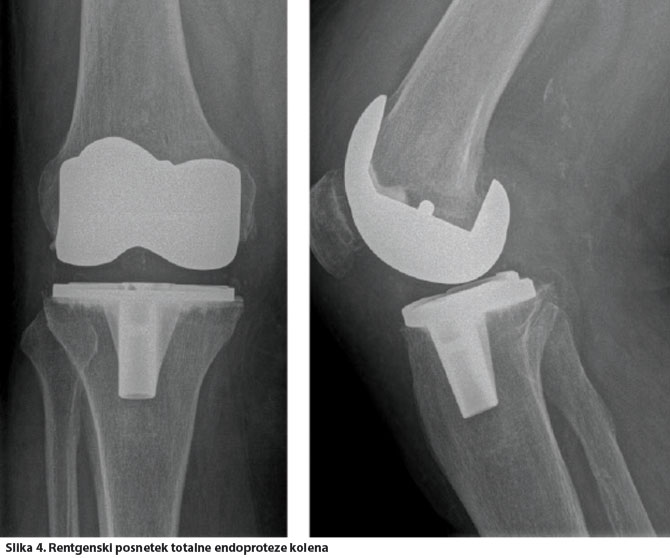

Totalna endoproteza kolena je operativna metoda, pri kateri obe sklepni površini obolelega sklepa nadomestimo z umetno protezo, ki jo čvrsto fiksiramo v kost. Tako obnovimo gibljivost sklepa ter funkcijo mišic, ligamentov in drugih mehkotkivnih struktur, ki nadzirajo sklep.

Umetni kolenski sklep je sestavljen iz femoralnega (stegneničnega) in tibialnega (goleničnega) dela, ki sta kovinska, med njima pa je polietilenska ploščica. Oba kovinska dela sta čvrsto fiksirana na kost s kostnim cementom, pri mlajših s čvrsto kostjo se lahko odločimo tudi za brezcementno učvrstitev. Občasno je treba vstaviti še tretji del na pogačico.

Po uspešno opravljeni rehabilitaciji je z vstavitvijo totalne endoproteze kolena omogočeno normalno življenje brez bolečin in brez posebnih omejitev. Odsvetujemo le pretirane in sunkovite obremenitve in aktivnosti, na primer težko fizično delo, tek.

Z vstavitvijo umetnega sklepa povrnemo gibljivost, odpravimo bolečino in popravimo deformacijo. Moderna totalna artroplastika kolena je uspešna operativna metoda, kar kažejo rezultati tako zgodnjih pooperativnih kot tudi poznejših (po desetletju in več) kontrol.